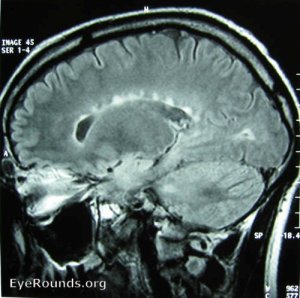

MRI of a patient with multiple sclerosis showing periventricular white matter lesions in the corpus callosum. Despite their size, such lesions are often asymptomatic and may be discovered incidentally.

From: EyeRounds Online Atlas of Ophthalmology, University of Iowa

Note: The above depicted pattern of white matter lesions was first described by another alumnus of the University of Edinburgh – James Walker Dawson (hence the name ‘Dawson’s fingers’).